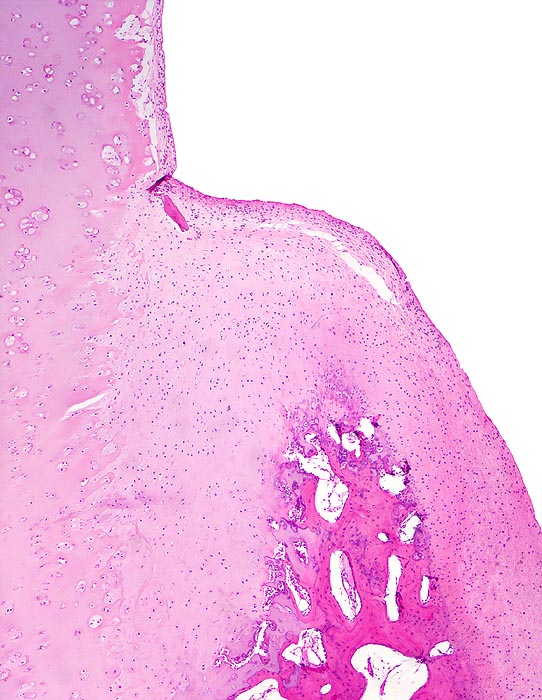

• Sekundäre Sklerose der freiliegenden Spongiosa mit Anbau von breiten Faser- und Lamellenknochensäumen an die alten Bälkchen.

• Leichte Osteoporose in der craniolateralen Entlastungszone.

• Herde von metaplastischem Faserknorpel in der Gelenkfläche.

• Randosteophyt, welcher über Resten des dort noch vorhandenen Gelenkknorpels entstanden ist (Verdoppelung des Knorpels).